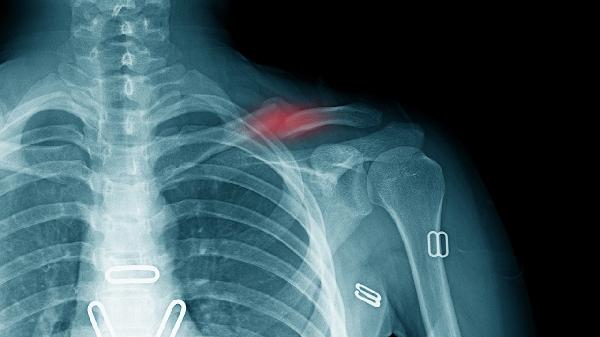

乳腺癌、肺癌、胃癌等恶性肿瘤可能通过淋巴道转移至锁骨下淋巴结。转移性淋巴结通常质地坚硬、活动度差、增长迅速且无压痛。左侧锁骨上淋巴结肿大需警惕胃癌转移可能。确诊需依靠淋巴结活检病理检查,治疗需针对原发肿瘤采取手术、放疗或化疗等综合措施。